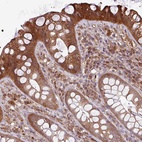

Immunohistochemical staining of human rectum shows cytoplasmic positivity in glandular cells.